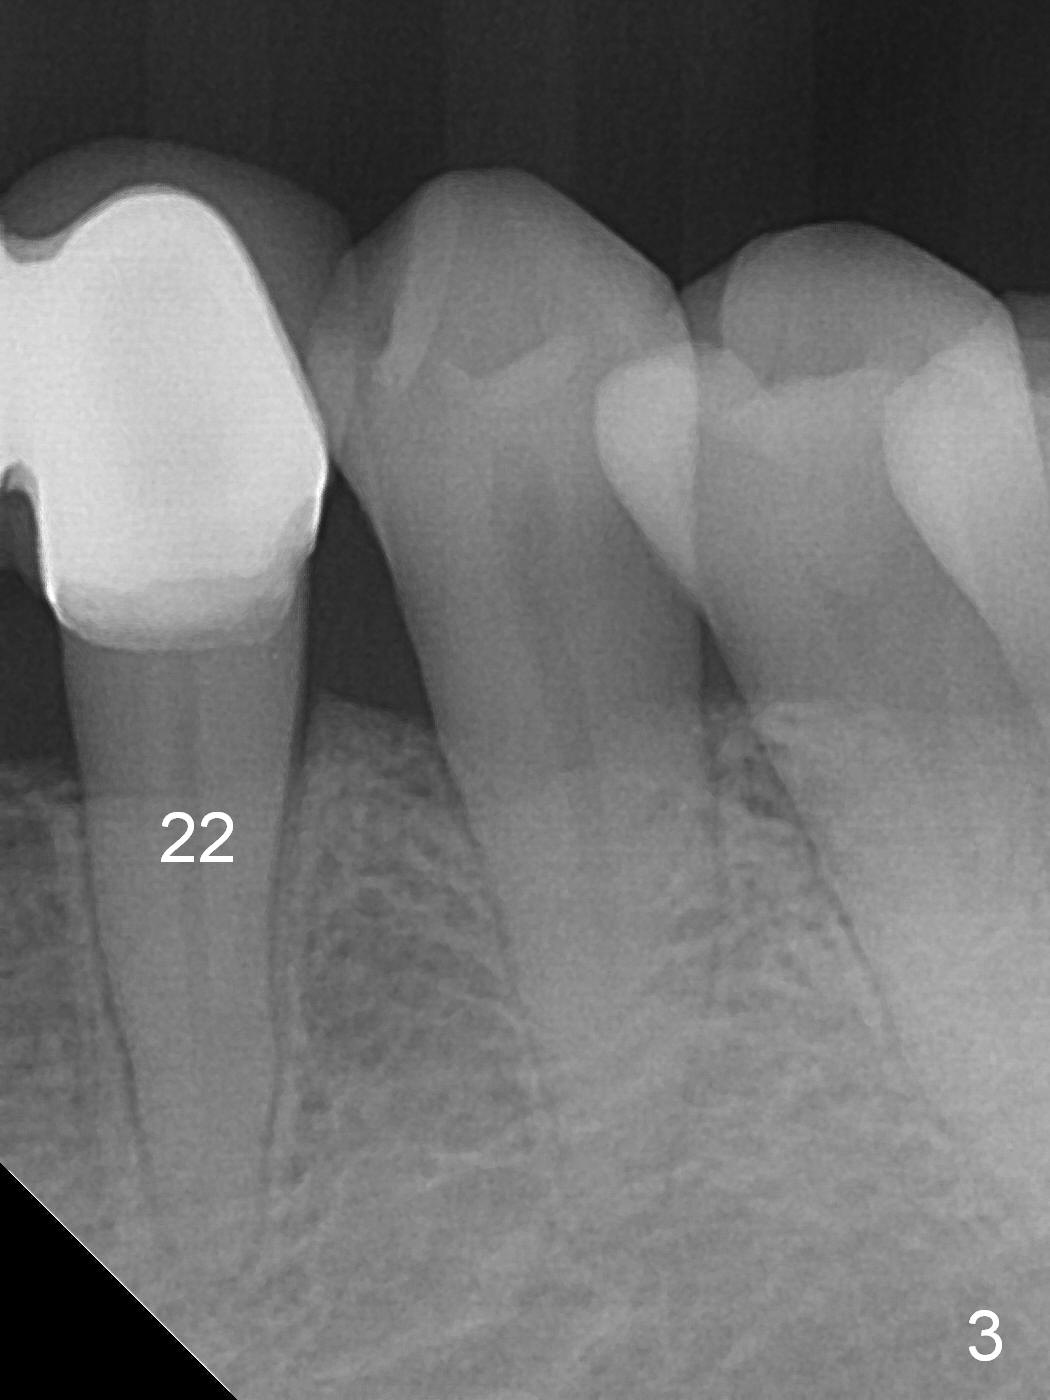

For the same token (severe bone loss at the mesial aspect of the site of #27), the site of #26 is not a good candidate one for implantation (Fig.2 *).  The site of #25 is most likely a better one.  The site of #23 should be the most favorite one among #23-26, since the edentulous site next to the dentate one is less likely resorbed after extracted.  For a FPD, abutments should be far away from each other.  No matter what, prepare 1-piece implants (as small as 2.5 and 2.0 mm ones) and surgical handpiece (why?).  Take preop photos to show recessive gingiva at #27.